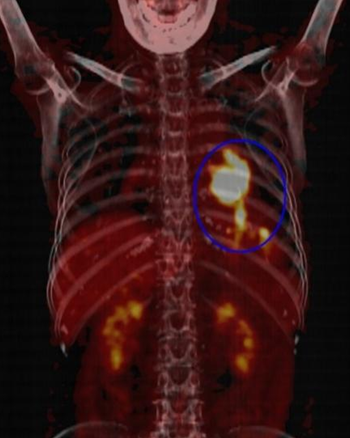

进行PET/CT检查后,医生通过PET图像、CT图像、PET/CT融合图像的阅片,胸骨呈术后改变,术区未见明显病变及显像剂的异常摄取,未见复发或残留(图2);右肺野近胸膜下可见多个边缘模糊的小结节,与前次CT片比较病变缩小,没有显像剂的异常摄取,符合良性病变。同时,发现宫颈处有斑片状的异常显像剂摄取,密度没有异常,考虑占位性病变(图3)。诊断医生再次询问李阿姨及家属,患者于48岁停经,目前没有异常引道流血等妇科症状,建议进行妇科检查。之后完成盆腔磁共振检查及宫颈活检,病理诊断为宫颈鳞状细胞癌,临床分期为IIA2期,经院内多学科会诊,依据诊疗规范,首选同步放化疗+阴道后装放疗的治疗策略。通过PET/CT检查,发现了胸腺瘤之外的第二原发恶性肿瘤,体现了PET/CT检查的高敏感性、高准确性,为临床更好地采取规范诊疗措施提供依据。

图2:红箭:胸骨术后改变;蓝箭:术区未见病变及异常代谢